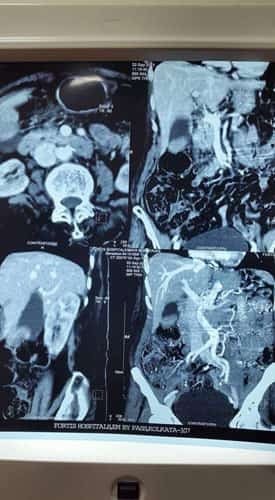

A Young lady who was a small kid...when her mother was operated for a Complex Gastrointestinal condition almost 14 years back by Dr Suddhasattwa Sen suddenly came in with severe blood loss from Gastrointestinal tract with a loss of almost 2 to 3 litres of blood with Shock with fainting . Further stabilisation was done and then extensive investigation revealed not only Piles and GI Ulcers but also SRUS Bleeding ulcers in rectum. A condition called Solitary Rectal Ulcer Syndrome ( a complex and difficult to cure anorectal problem ) . Her hemoglobin dropped to below 7 gm% She finally underwent surgery after 5 days and left home after 2 days post op without any further bleed or problems .